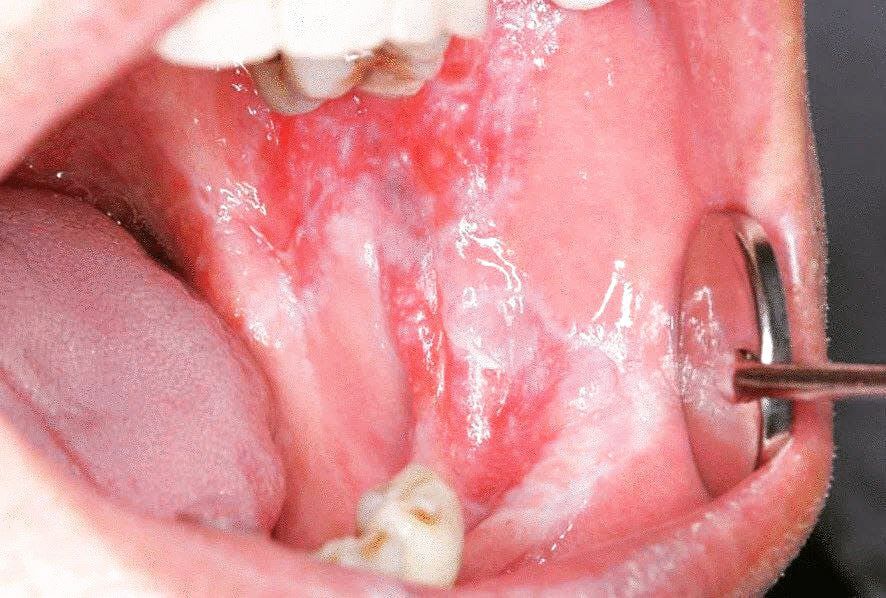

The typical erosive lesion of patients with oral lichen planus

Oral lichen planus (OLP) is a chronic inflammatory disease that affects the mucus membrane of the oral cavity. Oral lichen planus may appear as white, lacy patches; red, swollen tissues; or open sores. These lesions may cause burning, pain or other discomfort.